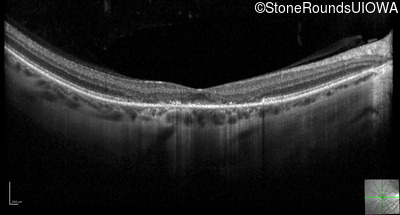

Optical Coherence Tomography - Left - 20/125

Exemplar / OCT Stack